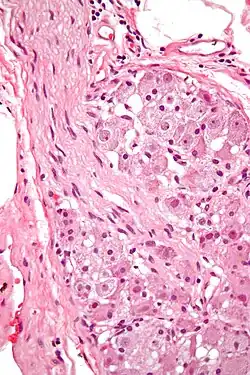

Various forms of nerve cells.